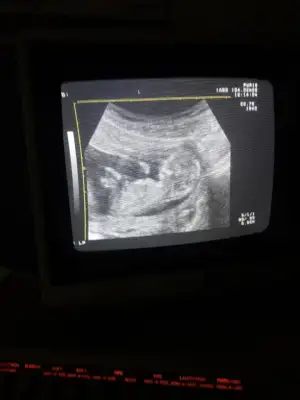

11 haftalikken kiz demistiniz ve Evet 18+4 te doktor kiz bebek dedi ☺Kız gibi diyorum net degil usg başka varmı 12+ hafta usgde paylaşın

Kız gibi tam net degil başka ush paylaşın 12 de olır13+1 sizce ?

Kız gibi gibi kaç haftalık bu usgBu arkası dönük olmazmi![]()

Başka usg varmı çok net değil diklik görünüyor sanki erkek gibi emin olamıyorum12 haftalık acaba cinsiyet tahmininde bulunabilir misiniz

Başka usg varmı çok net değil diklik görünüyor sanki erkek gibi emin olamıyorum